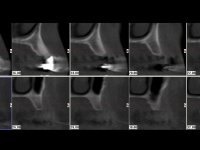

Realizada uma TAC, foi planificada a colocação de 6 implantes no maxilar superior. Foi decidida a colocação de dois implantes na zona dos incisivos centrais, dois implantes na zona dos caninos e dois na zona dos segundos pré-molares. A ausência de estrutura óssea na zona distal do primeiro quadrante implicava a realização de uma regeneração óssea no seio maxilar direito. A cirurgia foi realizada e após a colocação dos implantes foi feita a impressão para confeção de uma prótese provisória metalo-acrílica aparafusada para colocação em carga imediata no dia seguinte. O implante colocado na zona do seio maxilar direito não foi colocado em carga. Passados 6 meses foi realizada a impressão aos 6 implantes com técnica de moldeira aberta e foram confecionados os modelos de trabalho. Numa consulta seguinte foram montados os modelos de trabalho em articulador semi-ajustável utilizando o arco facial e a relação inter-maxilar obtida com a prótese provisória. Foi feita uma muralha de silicone sobre a ponte provisória com o objetivo de orientar o trabalho laboratorial. Realizada a infra estrutura metálica aparafusada esta foi provada em boca e finalmente após colocação de cerâmica o trabalho foi colocado definitivamente. Como passaram vários meses após a realização da primeira TAC foi feita uma segunda para planificar a colocação de implantes no 4º quadrante. Colocaram-se 3 implantes na mesma sessão em que foi feita a extração dos pilares da ponte. Estes implantes foram posteriormente reabilitados com uma ponte metalo-cerâmica aparafusada de três elementos.